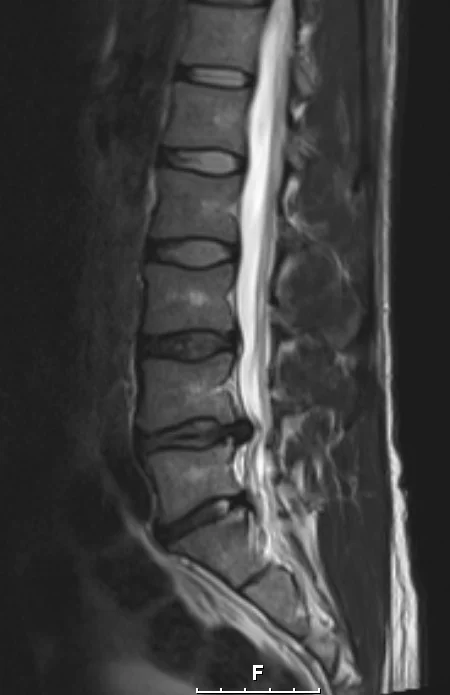

Kuin kaksi marjaa. Kuvien välissä yli 4 kk ja eteenpäin on menty...tai sitten ei. "Kyllä ne välilevynpullistumat itsestään kuivaa pois". "90% välilevynpullistumista paranee oireettomiksi 3 kk:ssa" :jahas: Sinällään jännä juttu että oireet ovat muuttuneet. Nyt en pysty enää istumaan hetkeäkään, mutta kävely onnistuu kivutta jos en istu.

Lekuri sanoi näiden viime kuvien jälkeen ettei kuvien perusteella mitään edistymistä/muutosta, mutta ei sitä kuvia leikata vaan oireita. On tosiaan jännä juttu miten kuvat on lähes identtiset 4 kk välillä, mutta nyt selkä on viikossa parantunut huomattavasti. Viime viikon maanantaina selkä oli kivuliain mitä se on koskaan aikaisemmin ollut. Makasin noroviruksen takia vessan lattialla yön yli ja seuraavana päivänä en pystynyt liikkumaan. Viikko sitten sattui niin saatanasti istua magneettikuvien jälkeen bussissa, mutta viikonloppuna kävin ensimmäistä kertaa tänä talvena lautailemassa. Itseasiassa kävin kahtena päivänä lautailemassa. Laskin lähes täydellä teholla, koska ajattelin ottaa komeasti viimeisen kerran kun olen laudan päällä. No, eipä tuo mennyt alkuunkaan huonommaksi.

Radiologin lausunnon mukaan siis prolapsi on kasvanut jonkun verran edelliseen kuvaan verrattuna ja sen takia paikat ovat voimaakkasti ahtautuneet. En todellakaan valita, mutta omituista kieltämättä että oireet ovat nyt helpottaneet. Jalkaa en pysty edelleenkään nostamaan aamulla kuin sen noin 30-40 cm ylöspäin. Iltapäivällä jalka heilahtaa kivutta 90-asteen kulmaan. Tunto on tallella, mutta akillesjänteen refleksi edelleen död ja tuskin enää palautuu koskaan. Mutta ei sillä mitään virkaa muutenkaan ole. Tästä on hyvä jatkaa kohti uusia loukkaantumisia :)